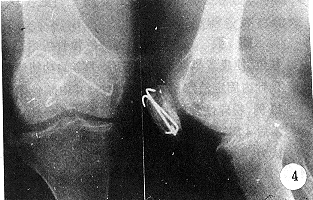

患者 女,61岁。因左膝关节摔伤后疼痛肿胀,功能障碍4小时入院。检查:左膝关节肿胀,压痛明显,可触及髌骨骨折线。X线片示髌骨粉碎性骨折。入院后6天行切开复位股四头肌腱膜条张力带克氏针内固定术。术后切口Ⅰ期愈合。术后4周下床活动。随访10个月,髌骨愈合良好,左膝关节活动正常(图3,4)。

本组52例,随访6个月~13个月,平均8个月。骨折愈合最短5周,最长9周,平均7.5周。术后4周~6周膝关节活动均达到正常或接近正常范围。按胥氏综合评定标准,本组优48例,良4例。

图4 术后8个月正、侧位X线片